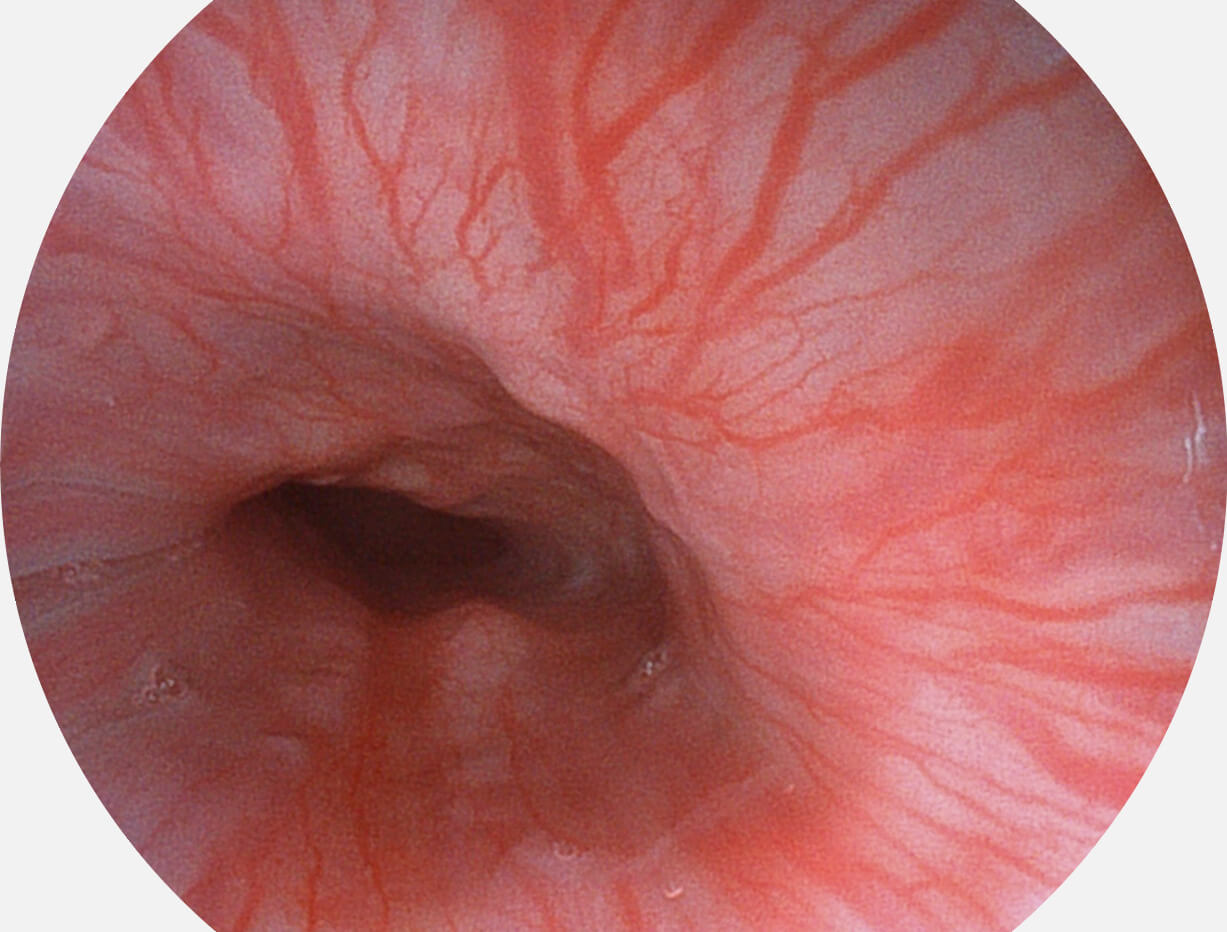

白光图像

VIST图像